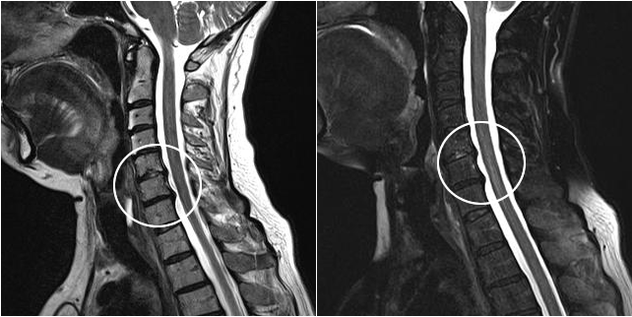

Moderne diagnostische methoden omvatten MRI en CT, die het mogelijk maken om de processen van vernietiging van kraakbeen- en botweefsel zo nauwkeurig mogelijk te onderzoeken. Met deze techniek is het ook handig om hernia's en andere defecten aan zacht weefsel dichtbij de bron van de ziekte te diagnosticeren.